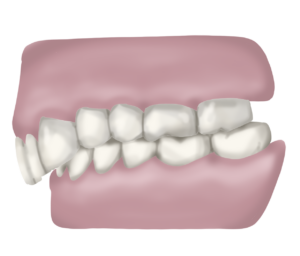

Mossegada oberta

La mossegada oberta la reconeixem perquè les dents de dalt no contacten amb les de baix, això es pot donar a nivell anterior o bé a nivell lateral/posterior de l’arcada dentària.

Perquè és un problema la mossegada oberta?

La mossegada oberta no és una mossegada equilibrada ja que no contacten totes les dents que haurien de contactar i això obliga a una part de les dents a treballar en excés i a l’altre part a no treballar. A part d’això pot generar una sèrie de tensions muscular i lligamentoses a nivell de la mandíbula, articulació temporomandibular i cervicals que portin a estats de dolor, clics o inclús que es transmetin a la resta del cos a través de les cadenes musculars provocant problemes a distància.

Quan un ésser arriba a la consulta amb mossegada oberta el primer que fem és buscar la causa d’aquesta: sempre trobem una llengua que es col·loca entre les dents, tant a l’hora d’empassar saliva, com a l’hora de parlar, com mentre descansem i no la fem servir. En aquest cas la llengua presenta una funció alterada que cal reeducar. Moltes vegades també s’hi suma un hàbit de respiració bucal, que caldrà tractar amb les mateixes premisses que hem explicat a l’apartat anterior, fent un acompanyament per a la reeducació respiratòria.

Igual que la respiració, la llengua és un múscul que funciona de manera inconscient i automàtica i per reeducar-la s’ha de treballar de manera conscient i regular, cada dia fer alguns exercicis. No n’hi ha prou portant l’activador.

Un activador plurifuncional ens obliga a col·locar correctament la llengua però quan el portem només durant la nit de manera inconscient no estem reeducant l’hàbit de manera veritable, cal fer-ho de manera proactiva i durant el dia.

A part de l’activador, als individus que tenen un hàbit lingual alterat, els proposem sessions de logopèdia regularment per acompanyar el tractament amb l’activador.

D’aquesta manera accelerem la resolució del problema a nivell dental i també ens assegurem que no es tornin a col·locar malament les dents un cop acabem el tractament.

Perquè està comprovat que gran part dels casos de recidiva post ortodòncia son deguts a una mala col.locació de la llengua. Doncs aquesta és un múscul molt potent i si cada cop que empassem impacta contra les dents en comptes de fer-ho contra el paladar les mourà molt més ràpid que qualsevol sistema de ortodòncia perquè la força que té la llengua és molt més significativa.